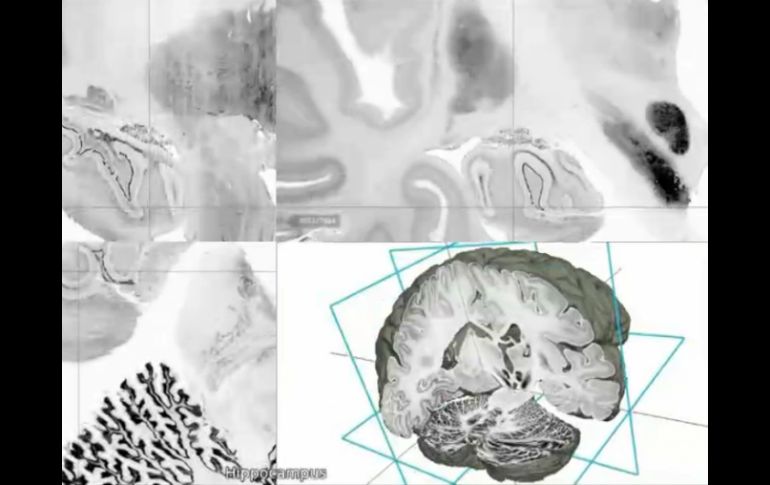

Tecnología | Dan a conocer la primera cartografía de alta tecnología de este órgano Presentan modelo de cerebro humano en 3D y alta resolución Dan a conocer la primera cartografía de alta tecnología de este órgano, 50 veces más precisa que las imágenes conocidas Por: AFP 20 de junio de 2013 - 20:16 hs BigBrain es el primer modelo con una representación realista de este órgano con las células de todas las estructuras cerebrales. AP / WASHINGTON, ESTADOS UNIDOS (20/JUN/2013).- Un equipo internacional de investigadores presentó el jueves el primer modelo del cerebro humano en 3D con una resolución microscópica, 50 veces más precisa que las imágenes conocidas hasta el momento y que permitirá el desarrollo de nuevas terapias contra las enfermedades neurológicas. Esta cartografía cerebral creada por científicos alemanes y canadienses, bautizada "BigBrain", contiene 100 mil veces más datos que un análisis de resonancia magnética. "BigBrain es el primer modelo de cerebro humano en 3D que constituye una representación realista de este órgano con las células de todas las estructuras cerebrales", subrayó Karl Zilles, de la Julich Aachen Alliance, en Alemania y uno de los principales autores del estudio publicado en la revista estadounidense Science del 21 de junio. El modelo de cerebro virtual está basado en informaciones procedentes de más de siete mil 400 cortes de tejido cerebral de a penas 20 micrones (el micrón es una millonésima parte del metro) extraídos del cerebro de una mujer de 65 años. Los cortes fueron digitalizados con un escáner de alta resolución. El modelo en tres dimensiones del cerebro se parece a un "andamio anatómico" de las estructuras y circuitos nerviosos cerebrales, que los científicos podrán seguir completando y utilizando en sus investigaciones contra el Alzheimer o el Parkinson. "Mejoramos considerablemente la representación de cerebro más allá de lo posible a finales del siglo XX", subrayó Alan Evans, profesor del Instituto de Neurología de Montreal y de la Universidad McGill en Montreal, otro de los autores del proyecto. "BigBrain va a revolucionar nuestra capacidad para comprender la organización interna del cerebro", afirmó. El proyecto científico forma parte de una iniciativa europea lanzada en 2013 y que busca crear la mayor instalación experimental del mundo para la reproducción del cerebro en alta precisión, el estudio de su funcionamiento y el desarrollo de tratamientos contra las enfermedades neurológicas. Estados Unidos lanzó un programa similar el pasado abril y China ha abierto una línea de investigación en este campo. Temas Ciencia Cerebro Tercera dimensión Lee También Nobel de Química premia el desarrollo de estructuras metal-orgánicas Nobel de Física para Clarke, Devoret y Martinis por descubrimiento sobre fenómenos cuánticos Nobel de Medicina premia investigación sobre el control del sistema inmunitario ¿Qué desencadena el párkinson en el cerebro? Científicos lo explican Recibe las últimas noticias en tu e-mail Todo lo que necesitas saber para comenzar tu día Registrarse implica aceptar los Términos y Condiciones